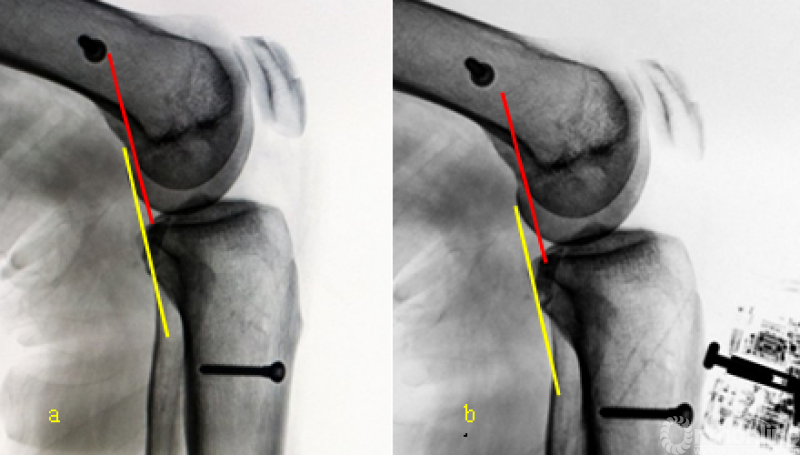

a 屈曲60°侧位片

b 后向300N应力侧位片

*红线表示股骨髁后缘线

*黄线表示胫骨平台后缘线

*连续镜下观察移植韧带无明显拉伸